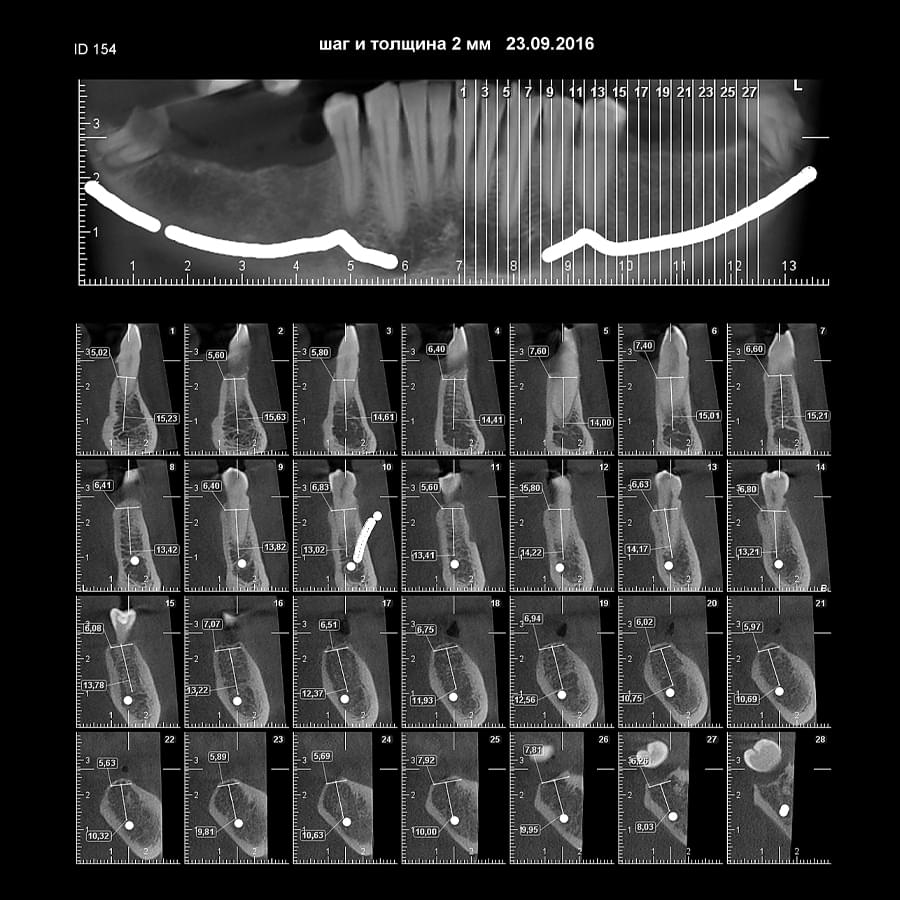

Комп'ютерна томографія

Щелепно-лицева діагностика

Ми використовуємо найсучасніше обладнання відомого виробника PLANMECA, що дозволяє отримувати високоякісні зображення за короткий час. Крім того, ми маємо власний сервер, на якому створюємо окрему скриньку для кожного лікаря, що забезпечує максимальну зручність та ефективність роботи.